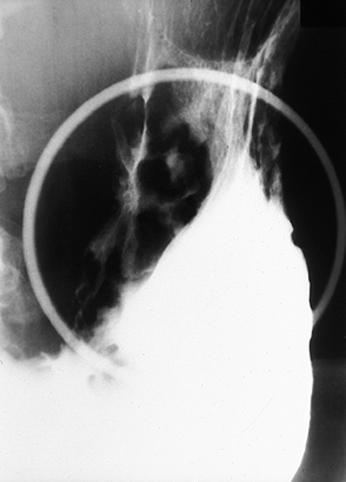

Linfoma Maligno del Estómago, que muestra la variada formación

[Image-ID:9324]

Tumor Maligno del Sistema Linfático/Linfoma Maligno

estómago(región)/mas de dos

Rayos X

40 -

s(a)